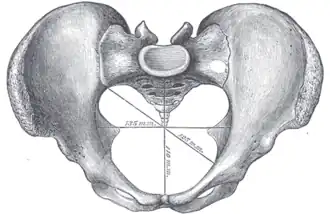

Additional images

Diameters of pelvic inlet